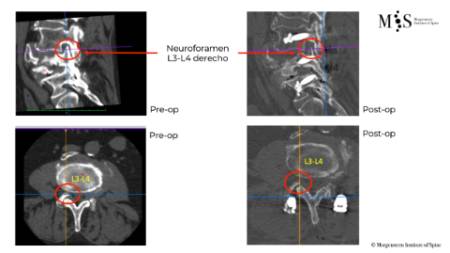

Vertebral body resection (corpectomy) and reconstruction of complex vertebral and burst fractures

Severe vertebral body fractures, i.e. conminute and burst fractures, may require a partial vertebral body resection (corpectomy) and reconstruction with an expandable vertebral body cage. Especially severe fracture cases are also those with a bone fragment moving into the spinal canal that compresses on neural structures, such as the spinal cord and causes spinal canal stenosis. Corpectomy allows to resect most of the fractured body, including the bone fragments pushing on the nerves and intruding into the spinal canal. The vertebral body reconstruction is usually rounded up with a posterior augmented instrumented fusion of the adjacent levels to the fracture. All of this allows a proper healing of the fracture and the patient to recover without pain.

Clinical case example of a lumbar vertebral body resection (corpectomy) and reconstruction of a burst fracture at level L4.